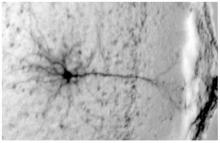

Actualité publiée il y a 7 années 6 moisPHTALATES : Exposition périnatale et destruction neuronale